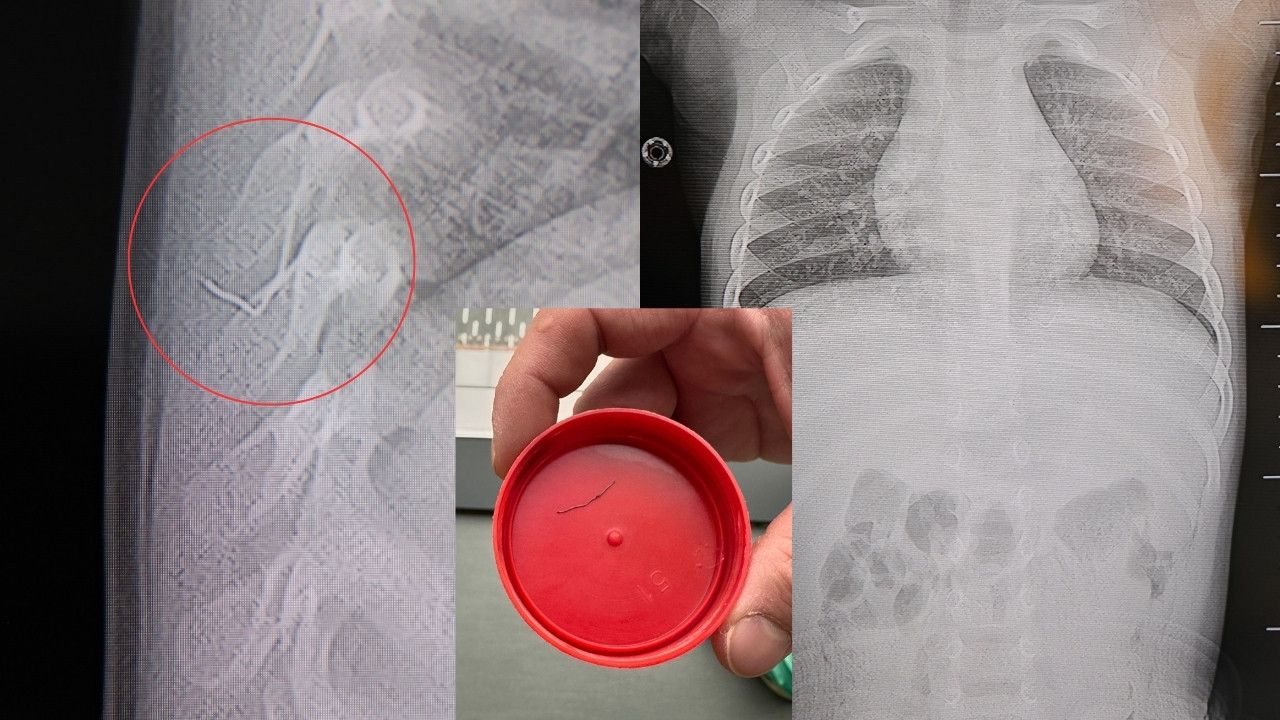

TEL, OMURİLİK KANALINA YAKIN VE AKCİĞER ZARINA DAYANIYORDU

Prof. Dr. Altun’un değerlendirmelerine göre, söz konusu metal tel; bebeğin omurilik kanalına çok yakın, akciğer zarına doğru ilerleyen bir noktadaydı. Bu bölgede gelişebilecek enfeksiyonun hayati risk taşıyabileceği, hatta ilerleyen yaşlarda ciddi omurilik hasarlarına neden olabileceği bildirildi.

“Hastayı tamamen uyutmadan, lokal anestezi ve sedasyon altında müdahale ettik. Cilt altından çıkarılan yabancı cisim yaklaşık 2 santimetre uzunluğunda, zımba teline benzer bir metal parçaydı. Bu tel alınmasaydı, enfeksiyon, omurilik hasarı, akciğere batma ve hatta tümör benzeri reaksiyonlara yol açabilirdi” dedi.

Daha önce farklı hastanelerde “beklemek gerekir” denilen durumu önemseyen aile, farklı bir değerlendirme için tekrar uzman görüşü aradı. HG Hospital’de yapılan detaylı görüntüleme sayesinde telin riski net bir şekilde ortaya kondu. Başarılı operasyon sonrası bebek, aynı gün taburcu edildi.